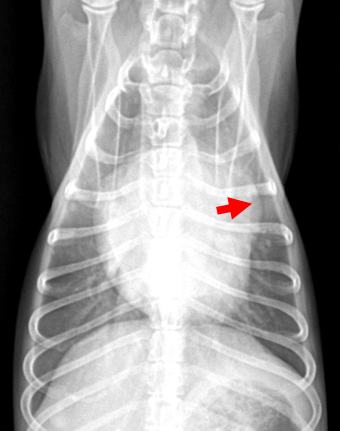

영상

소견

- VD view의 1시 방향에 있는 mPA 커짐

- 심장 초음파로 duct 크기 판단 가능. Ao:mPA=1:1 이 정상인데, 폐동맥이 더 커짐.

- 좌심방이 더 커짐. (⇒ 심전도에서 P파가 넓어진 mitral P)